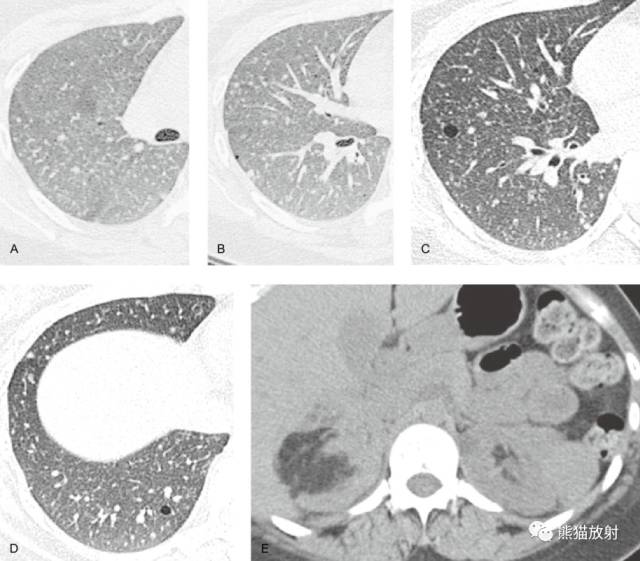

LAM中的肺囊肿与肺朗格汉斯细胞组织细胞增生症(PLCH)中描述的非常相似然而,3种表现常可以区别这两种疾病。

PLCH是一种少见病,常发生在20-40岁的年轻人中,虽然可发生在任何年龄。PLCH以往被称为肺嗜酸性肉芽肿、肺组织细胞增生症X,其典型表现为孤立的,累及单器官的病变,虽然也可是多器官、多系统疾病的一种表现。

病变主要分布在上、中肺部,基底部相对不累及。